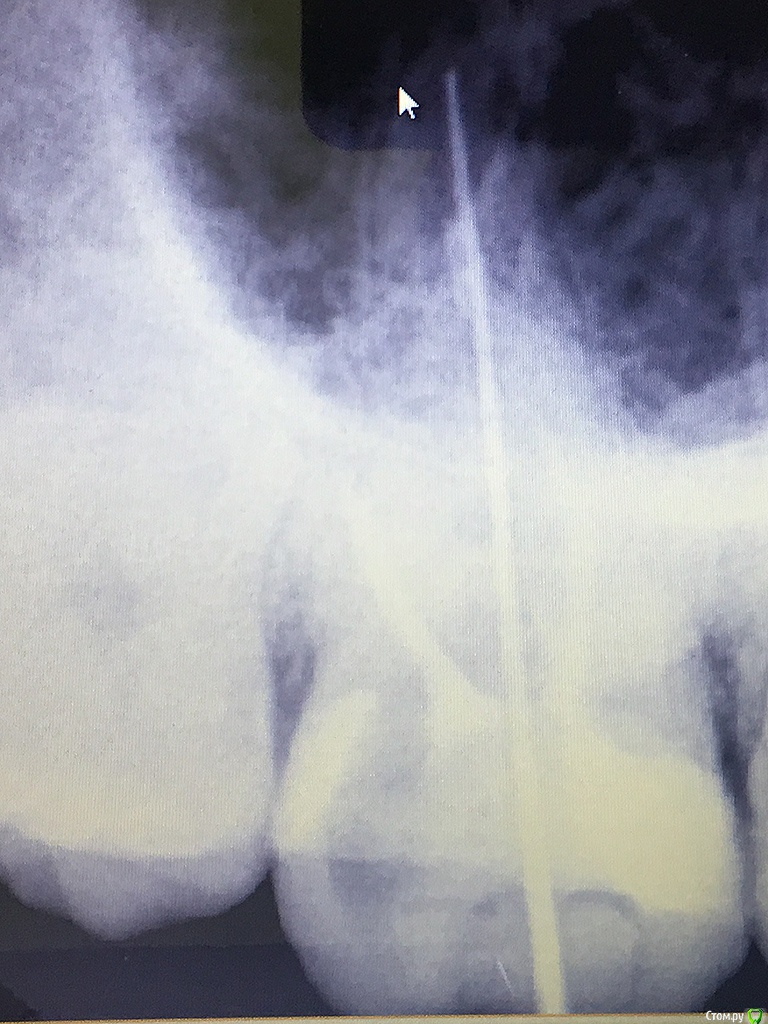

rozmari Опубликовано 20 марта, 2017 Поделиться Опубликовано 20 марта, 2017 Здравствуйте люди добрые.), пытаюсь пролечить верхнюю 7-ку с 14 октября (5 месяцев).Коротко о наболевшем:1. 10 октября выпала пломба, 14 октября пролечил кариес.После лечения зуб ныл после еды, ждали с врачом 1.5 месяца, но боли не прошли.2. 2 декабря положили лекарство, 16 декабря депульпировали зуб, прочистили 3 канала. Далее болей и нытья после еды нет, но не проходит чувствительность зуба, даже на легкое постукивание ногтем с любой стороны, так же неприятно реагирует на зубную щетку....ждемс3. 27 февраля симптомы не проходят, врач говорит пропить 3 дня Найс, пропито, ничего не изменилось. меняю клинику... 4. 9 марта делаю снимок №1 обнаруживаем не долеченный нёбный канал, чистим, ставим временную пломбу 5. 19 марта симптомы не изменились, 2 часа пытаемся прочистить оставшиеся 2 канала (безуспешно), зато с большими сомнениями, но вроде как нашли 4й канал(снимок №3), чистим и ставим временную пломбу. продолжение следует.....на приём через неделю п.с. вижу что качество снимков оставляет желать лучшее, но всё же буду очень благодарен любому совету. Ссылка на комментарий